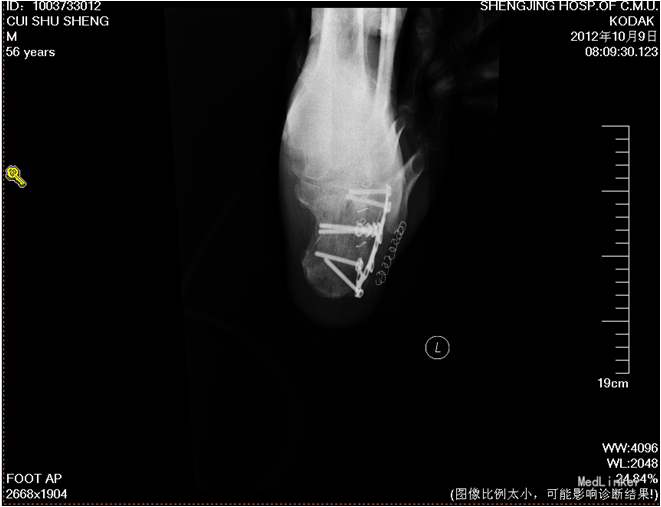

术后复查X线片示骨折复位良好,内固定在位且牢靠。根据骨伤科三期辨证理论,早期因瘀血停滞影响骨痂生长,故以活血化瘀,消肿止痛为主,应用桃红四物汤。术后证属肝肾亏虚,气血不足,治以补益肝肾,补气养血,应用愈骨胶囊等药物促进骨折愈合。术后嘱患者继续石膏托外固定,注意陪护,3月内扶双拐、按指导患肢不负重功能锻炼;休息3个月,加强营养,促进骨折愈合;继续中药应用,促进骨折愈合;定期复查,(1月、3月、6月);不适随诊。 本病例中医药应用结合手术复位,早期将骨折复位,中医药早期应用活血化瘀、消肿止痛,可迅速缓解患者症状。中医药中后期应用可促进骨折愈合,加快术后恢复,可使患者获得满意的术后疗效。